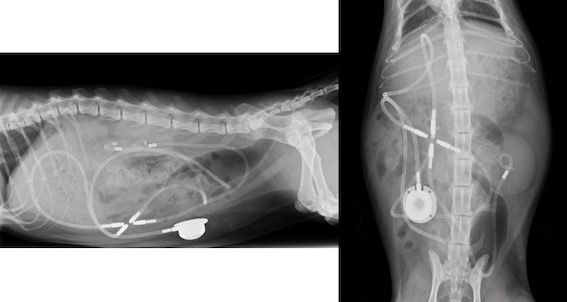

両側に設置した症例です。↓↓